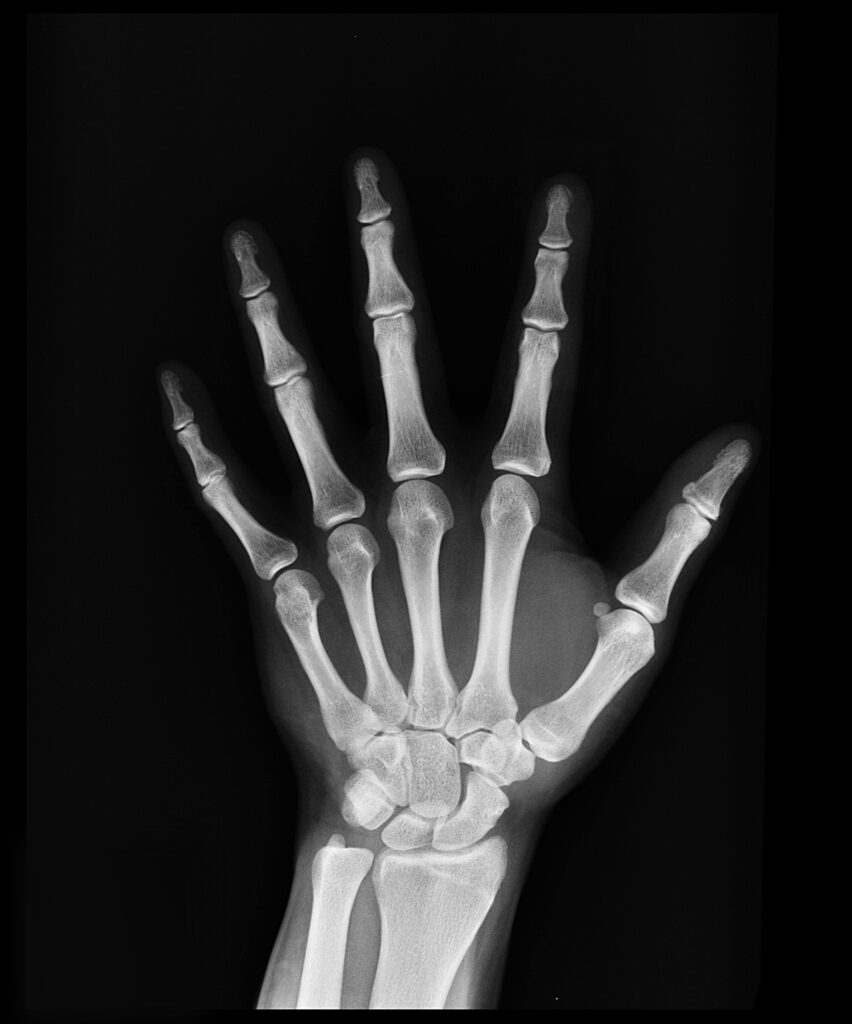

- Autopodium (distal limb): Carpals/Metacarpals/Phalanges (forelimb), Tarsals/Metatarsals/Phalanges (hindlimb)

- Limbs: Extreme specialization (e.g., bat wings, whale flippers, human hands)